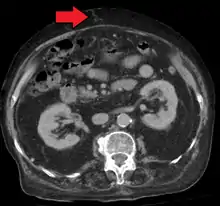

In addition, a widened (dilated) portal vein as seen on a CT scan or MRI may raise the suspicion about portal hypertension. A cutoff value of 13 mm is widely used in this regard, but the diameter is often larger than this is in normal individuals as well.[8]

Ultrasonography (US) is the first-line imaging technique for the diagnosis and follow-up of portal hypertension because it is non-invasive, low-cost and can be performed on-site.[13]

A dilated portal vein (diameter of greater than 13 or 15 mm) is a sign of portal hypertension, with a sensitivity estimated at 12.5% or 40%.[14] On Doppler ultrasonography, a slow velocity of <16 cm/s in addition to dilatation in the main portal vein are diagnostic of portal hypertension.[15] Other signs of portal hypertension on ultrasound include a portal flow mean velocity of less than 12 cm/s, porto–systemic collateral veins (patent paraumbilical vein, spleno–renal collaterals and dilated left and short gastric veins), splenomegaly and signs of cirrhosis (including nodularity of the liver surface).[13]

The hepatic venous pressure gradient (HVPG) measurement has been accepted as the gold standard for assessing the severity of portal hypertension. Portal hypertension is defined as HVPG greater than or equal to 5 mm Hg and is considered to be clinically significant when HVPG exceeds 10 to 12 mm Hg.[16]